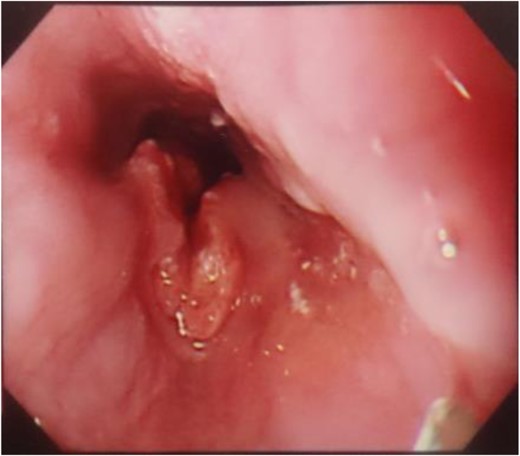

A 56-year-old man presented to our institution with esophageal and gastric cancer. Esophagogastroduodenoscopy (EGD) demonstrated a type 2 tumor occupying one-third of the circumference of the esophagus and measuring 28–33 cm from the incisors (Fig. 1). Endoscopy revealed that the tumor invaded the muscularis propria and biopsy revealed SCC. Moreover, a type 0-IIb tumor was located at the lesser curvature of the angle of the stomach. Endoscopy revealed invasion of the mucosa and biopsy revealed adenocarcinoma (Fig. 2). Computed tomography (CT) showed no enlarged lymph nodes in the mediastinum or distant metastasis in the liver or lung. Therefore, the patient underwent thoracoscopic esophagectomy (video-assisted thoracic surgery for esophagus), 2-field lymph node dissection, partial gastrectomy and gastric tube reconstruction via a retrosternal route for the advanced esophageal and early gastric cancers. Histopathologic analysis revealed Stage II (type 2, T3, ly2, v0, N0, PM0, DM0) esophageal and Stage I (type 0-IIb, T1, ly0, v0, N0) gastric cancer, with positive horizontal margins of dissection of the gastric cancer. Therefore, as additional treatment, we performed argon-plasma coagulation around the dissected gastric mucosa postoperatively.

A type 2 tumor occupying one-third of the circumference of the esophagus on esophagogastroduodenoscopy.